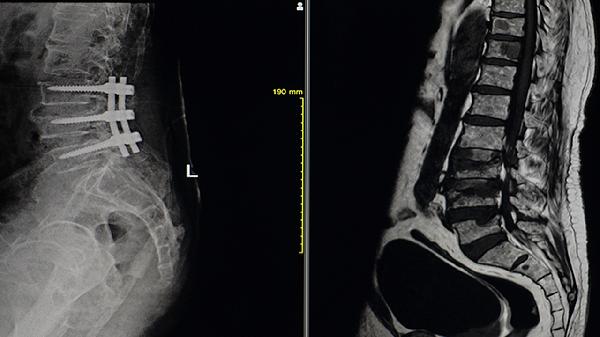

3、手术治疗

当强直性脊柱炎严重影响生活质量和工作能力时,手术治疗可能是必要的选择。手术可以矫正畸形,恢复功能。手术的决定需要经过详细的评估和医生的专业建议。